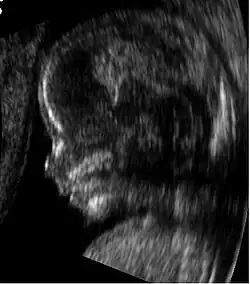

As opções de exame de imagem na gravidez incluem:

- Ressonância magnética (RM) sem meio de contraste em RM e ultrassonografia obstétrica não estão associadas a nenhum risco para a mãe ou para o feto e são as técnicas de imagem de escolha para gestantes.[1]

Ressonância magnética

A ressonância magnética (RM), sem meio de contraste em RM, não está associada a riscos para a mãe ou o feto e, juntamente com a ultrassonografia médica, é a técnica de escolha para exames de imagem na gravidez.[1]

Usos comuns

A RM é frequentemente utilizada em gestantes com dor abdominal e/ou dor pélvica aguda, ou em casos suspeitos de doença neurológica, doença placentária, tumores, infecções e/ou doença cardiovascular.[3] Os critérios de uso apropriado do Colégio Americano de Radiologia dão nota ≥7 (geralmente apropriado) para RM sem contraste nas seguintes condições: